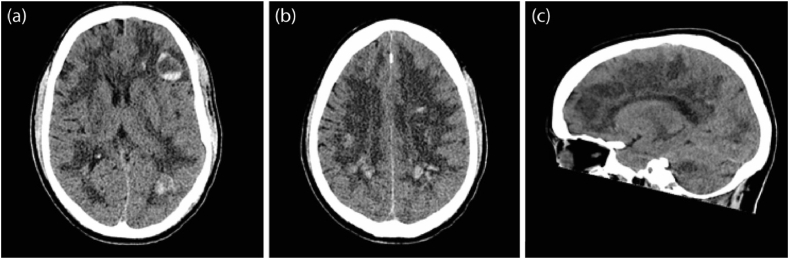

Computed tomography (CT) scan of the brain was performed on day 26 to investigate his persistently reduced GCS. This demonstrated probable Acute Haemorrhagic Leukoencephalitis (AHLE) (Fig. 1). Magnetic resonance imaging (MRI) brain (on day 27) and cerebrospinal fluid (CSF) analysis on day 30 were undertaken and neurosurgical and neurology opinions were sought.

Fig. 1.

First Computed Tomography (CT) scan of the head. (diffuse white matter hypodensity which possibly due to oedema or demyelination process, and multiple bilateral white matter haemorrhagic foci involving the corpus callosum with fluid blood level in some of them, with most of the blood is along the white matter venules).

Poyiadji et al. reported a case of acute haemorrhagic necrotizing encephalopathy (ANE) linked with SARS-COV-218 where the patient presented with altered conscious level and no abnormal findings on CSF analysis (Poyiadji et al., 2020). In our case, no focal neurological features were noted at presentation but high opening pressure at lumbar puncture, high CSF protein, and serum and CSF oligoclonal bands with additional bands in CSF were identified. Furthermore, a fatal case of ANE in COVID-19 has been reported. However, no oligoclonal bands were identified in their CSF analysis. The CT head showed brain oedema, whereas our case’s CT head showed multiple bilateral white matter demyelination, and haemorrhagic foci involving the corpus callosum as well as oedema (Elkady and Rabinstein, 2020)..(Needham et al., 2020)